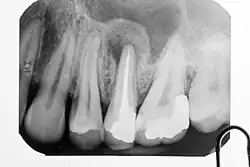

Apikale Parodontitis am kariösen linken unteren ersten Molaren (Zahn 36), ausgeprägt an der mesialen Wurzelspitze

Ursache

Wenn die primär chronische Form in eine akute Entzündung umschlägt, tritt ein typischer Klopfschmerz auf. Röntgenologisch sind apikale Aufhellungen meist erst nach mehrwöchigem Krankheitsverlauf zu erkennen. Als erstes Anzeichen ist ein erweiterter Periodontalspalt sichtbar. Veränderungen der Knochendichte sind im Röntgenbild erst erkennbar, wenn mindestens 30 % des Mineralgehaltes des Knochens abgebaut sind. Das kann bei einer apikalen Ostitis einige Tage bis Wochen dauern. Bei geringen Beschwerden und unsicherer Aussagekraft des Röntgenbildes ist eine Wiederholungsaufnahme erst nach drei Monaten angebracht.